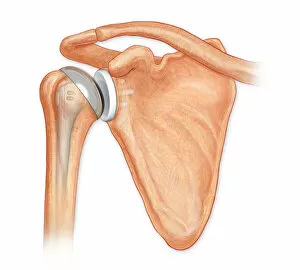

The scapula, also known as the shoulder blade, is a crucial bone in our body that plays a significant role in our mobility and stability. It forms part of the pectoral girdle and connects the upper arm to the thorax. When we examine diagrams of the bones of the hand and arm, we can see how intricately connected they are to the scapula. This connection allows us to perform various movements with precision and control. In an anterior view total shoulder joint repair image, we witness medical advancements aimed at restoring functionality to this vital joint. The intricate procedure highlights just how important it is to maintain a healthy scapula for optimal movement. Shoulder muscles artwork showcases their attachment points on the scapula, emphasizing their role in providing strength and stability during physical activities. Understanding these muscles helps us appreciate their contribution to everyday tasks like lifting or throwing. A front view of female anatomy highlighting the endocrine system reminds us that even though not directly related to the scapula, every part of our body works together harmoniously. Hormones secreted by glands within this system influence bone health and development. An anterior view of human skeletal system with labels gives us a comprehensive understanding of where exactly our scapula fits into this complex framework. It serves as an anchor point for numerous ligaments and tendons essential for proper functioning. Pictograms on an ox scapula depict ancient rituals performed to ward off danger—a testament to how cultures throughout history recognized its significance beyond mere anatomy. These artifacts remind us that humans have long understood its importance in daily life. The skeleton of an eagle after Milne-Edwards engraving demonstrates nature's adaptation at its finest—the bird's wingspan relies heavily on strong shoulder blades (scapulas) allowing it effortless flight through vast skies. Haydon's Curtius engraving captures another artistic representation showcasing human form—this time focusing on muscular structure including the scapula.